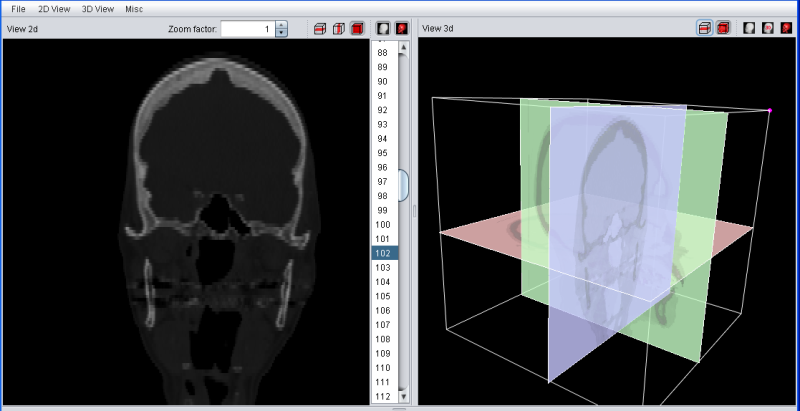

The Ortho Slice Mode will looks similiar, but also show the last selected slices in transversal, saggittal and frontal mode.

An enhanced 3D visualzation feature is the 2D-Texture Visualization. It basically renders several slices in transversal, sagittal and frontal projection with a low transparency value, allowing a fast and 3 dimensional analysis of the loaded data set. It can be enabled using the "3d View" main menu or the button in the "View 3d" title bar.

The quality of the 2D-Texture Visualization strongly depends on the number of planes which are rendered. This can be choosen in the "View 3d" tab of the main tool pane. Select "1" for the best results - and the highest main memory consumtion. The overall transparency allows to look "through" the data to analyse internal structures and it is possible to choose between a "grey scale" and "pseudo color" colortable.